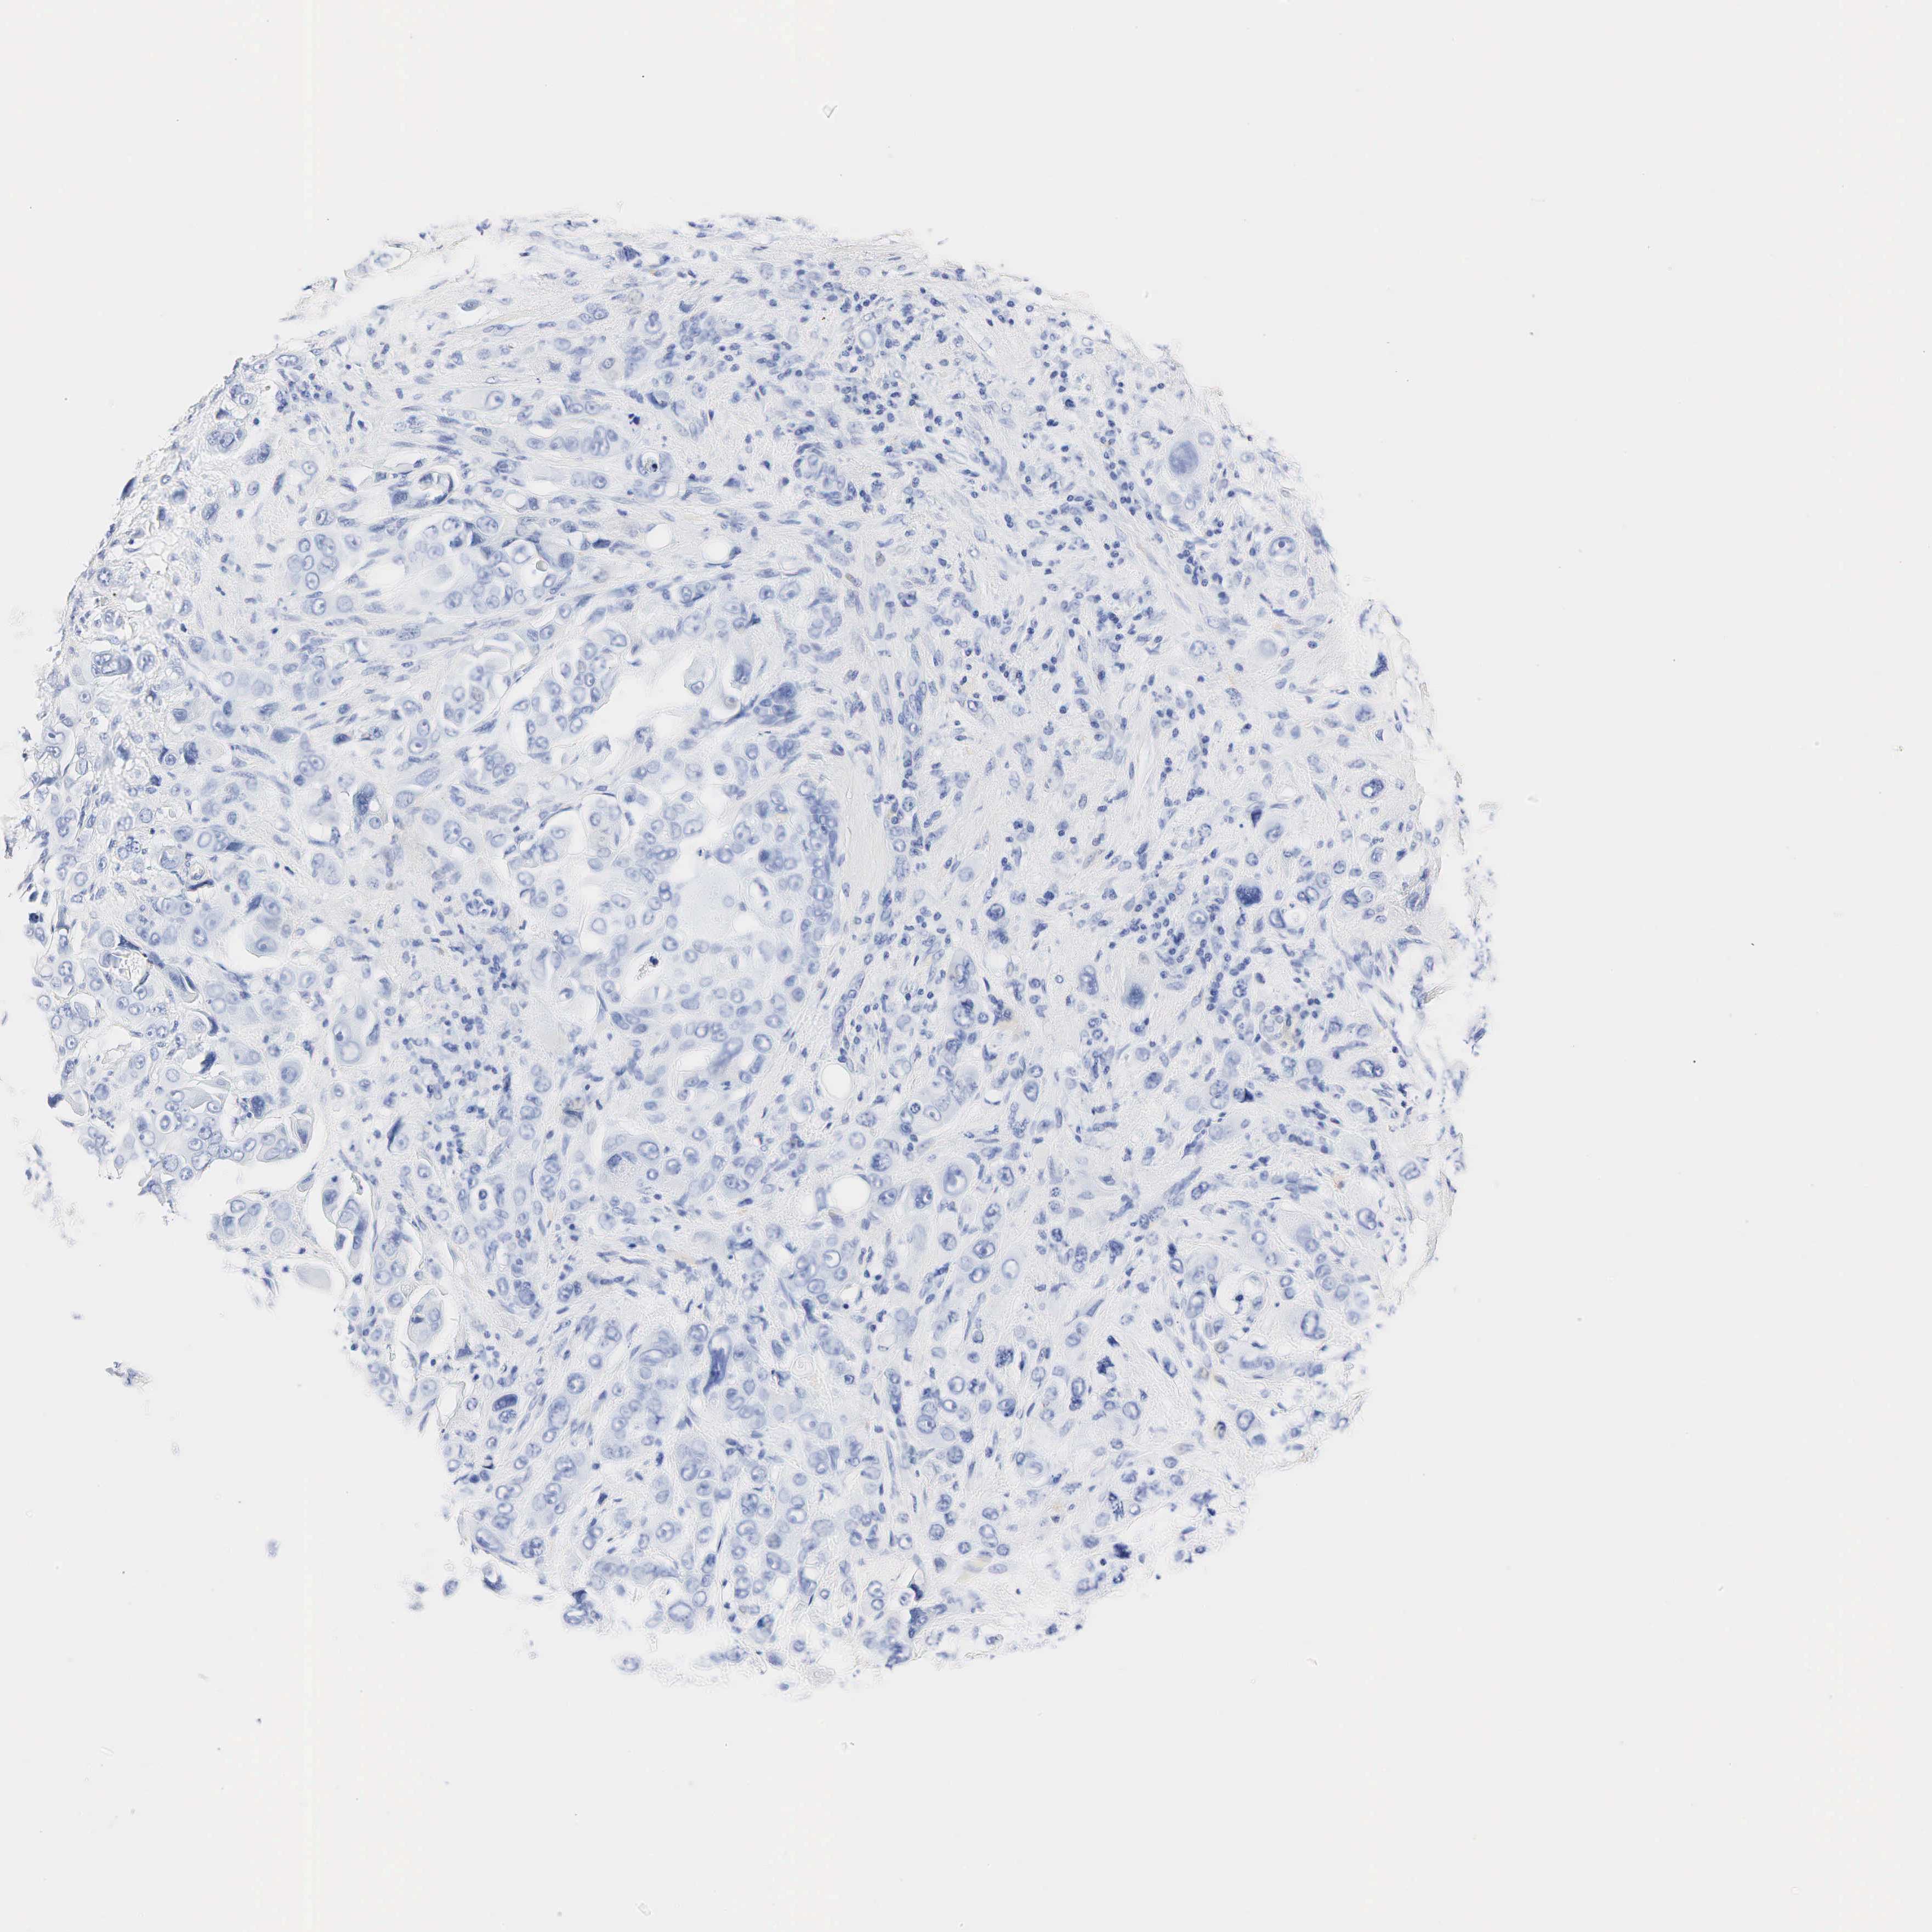

LIVER CANCER - Protein expressioni

A mouse-over function shows sample information and annotation data. Click on an image to view it in a full screen mode. Samples can be filtered based on level of antibody staining by selecting one or several of the following categories: high, medium, low and not detected. The assay and annotation is described here.

Note that samples used for immunohistochemistry by the Human Protein Atlas do not correspond to samples in the TCGA dataset.

Antibody stainingi

Antibody staining in the annotated cell types in the current human tissue is reported as not detected, low, medium, or high, based on conventional immunohistochemistry profiling in selected tissues. This score is based on the combination of the staining intensity and fraction of stained cells.

Each image is clickable and will lead to virtual microscopy that enables deeper exploration of all samples and also displays staining intensity scores, fraction scores and subcellular localization as well as patient and tissue information for each sample.

Antibody HPA002740

Antibody CAB000077

Antibody CAB056155

Staining

High

Medium

Low

Not detected

Intensity

Strong

Moderate

Weak

Negative

Quantity

>75%

75%-25%

<25%

None

Location

Nuclear

Cytoplasmic/membranous

Cytoplasmic/membranous,nuclear

Carcinoma, Hepatocellular, NOS

Cholangiocarcinoma

Carcinoma, metastatic, NOS